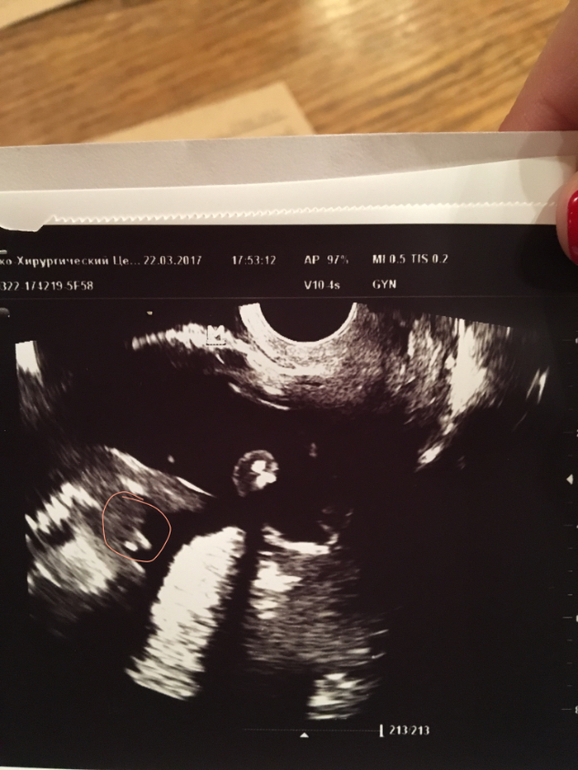

Пол малыша

Результаты: УЗИ, КТГ, доплера, скринингаДевочки, помогайте!

У кого глаз алмаз? Я ничего не понимаю, где чего у малыша . Выделила тк область, которая НА МОЙ ВЗГЛЯД, что-то говорит о поле маленького. (, 1фоткой мне вообще непонятно)

Фото под кат